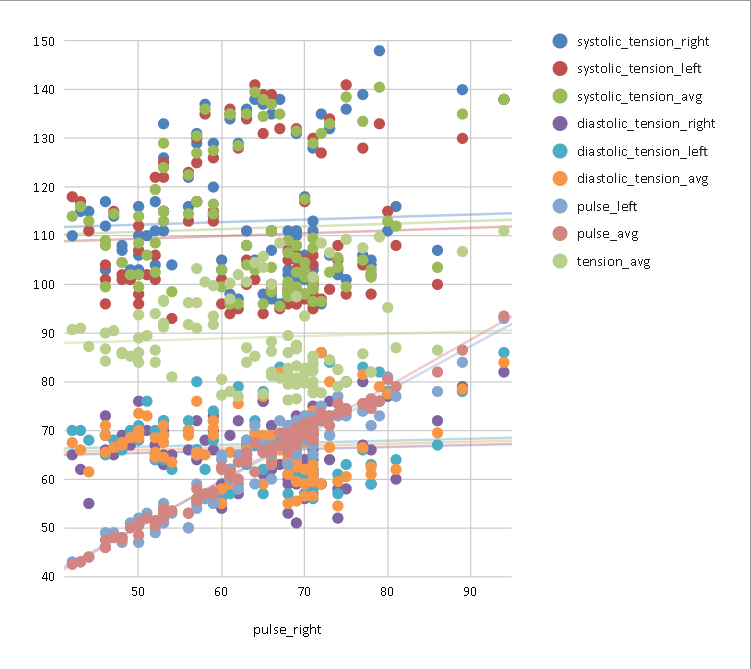

CVR and blood pressure

Due to its nature as homeostatic and cerebrovascular process, CVR is modulated by systemic changes in blood pressure¹

1. Fierstra et al. 2013 (J. Physiol.); 2. e.g. Hetzel et al. 1999 (Stroke)

Previous studies with Transcranial Doppler Ultrasound suggest to take into account blood pressure when measuring CVR²

To our knowledge, the impact of blood pressure on BOLD-fMRI based CVR estimation has not been assessed yet

Vital signs (VS), measured before the MRI session, while the subject was lying supine on a bed, once on the left arm and once on the right arm:

- Cardiac pulse

- Blood pressure (systolic and diastolic)

We averaged the two measurements and computed the Mean Arterial Pressure (MAP) and the Pulse Pressure (PP):

Correlation between VSs

Correlation between VSs

Results: blood pressure

Results: blood pressure

Results: blood pressure

Both MAP and PP should be taken into account in CVR experiments, especially in comparisons between subjects or between regions!

- Stationary blood pressure changes, expressed as MAP and PP, as well as sex, impact regional CVR estimation differently across sessions and subjects

Dynamic blood pressure changes are expected to impact CVR estimation, hence continuous blood pressure recordings are required to assess the matter